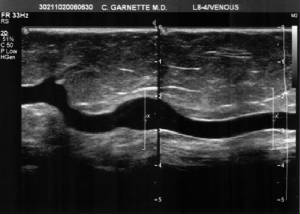

long_tort_aneur_gsv_split_scrn.jpg

Tortuous and aneurysmal greater saphenous vein